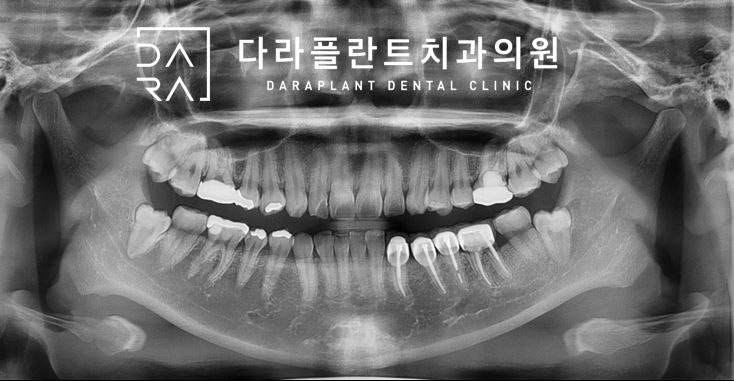

이렇게요. 생각보다 두꺼운 신경관이 치아 밑을 지나고 있어요. 마지막 단면 볼까요?

이렇게 보면 신경관이 어딘지 자세히 안 보여요.

바로 여기입니다. 위 그림에서 표현한 하악신경관에는 신경만 통과하는 것이 아니라 혈관도 함께 지나갑니다. 그리고 이를 통해서 아래턱 감각을 인지하거나 아래턱 뼈 부위에 영양분을 공급하기도 합니다.치과 치료를 하고 있으면 하악 감각 이상이 생기는 경우도 있습니다.이것은 대부분 위에서 나타낸 하악 신경의 손상에 의해 발생합니다. 따라서 치과의사는 아래턱 치료 또는 수술을 할 때 항상 조심스럽게 치료를 합니다. 어쨌든 환자분, 덕양구 사랑니 발치과 다라플랜트에서 좌측 상하 매복 사랑니 발치를 하도록 하겠습니다. 위에는 예상대로 바로 나옵니다.